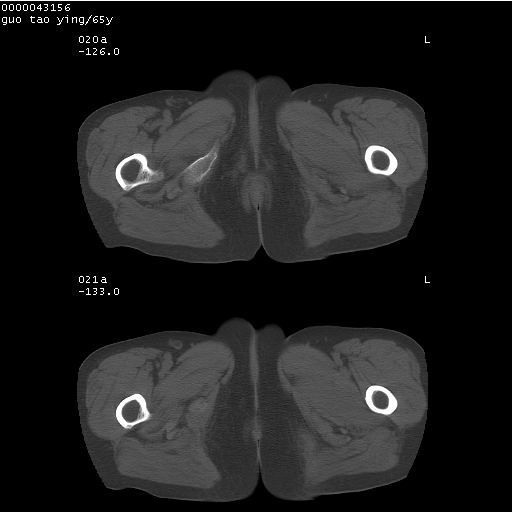

以下是引用黑白光影在2008-1-30 13:22:00的发言:[br]支持左耻骨骨折。[br]未见骶骨骨质明确破坏改变。[br]经楼主提示(勿局限于外伤)。考虑为右侧腹股沟直疝。[br][br][br][br]